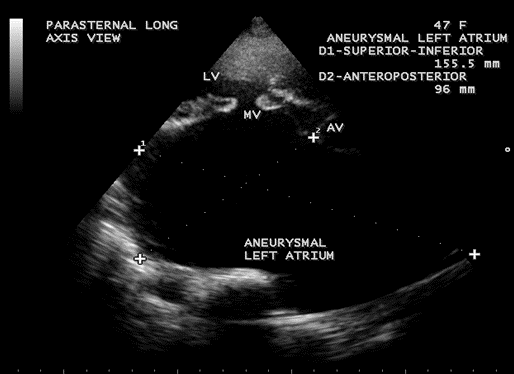

Figure 18. Parasternal long axis view showing the giant left atrium looks like a ‘crown (LV) on a cushion (aneurysmal left atrium)’ appearance in a 47-year-old female.

Figure 19. Parasternal long axis view showing the severe mitral regurgitation and giant left atrium in a 47-year-old female.

The balloon-like enlargement of the left atrium which occupied the whole of the posterior, right and left mediastinum and the rest of the heart looks like a ‘crown on a cushion’ as shown in Figures 17 and 18 in mixed mitral valve disease (both stenosis and regurgitation) as in Figures 19 and 20.